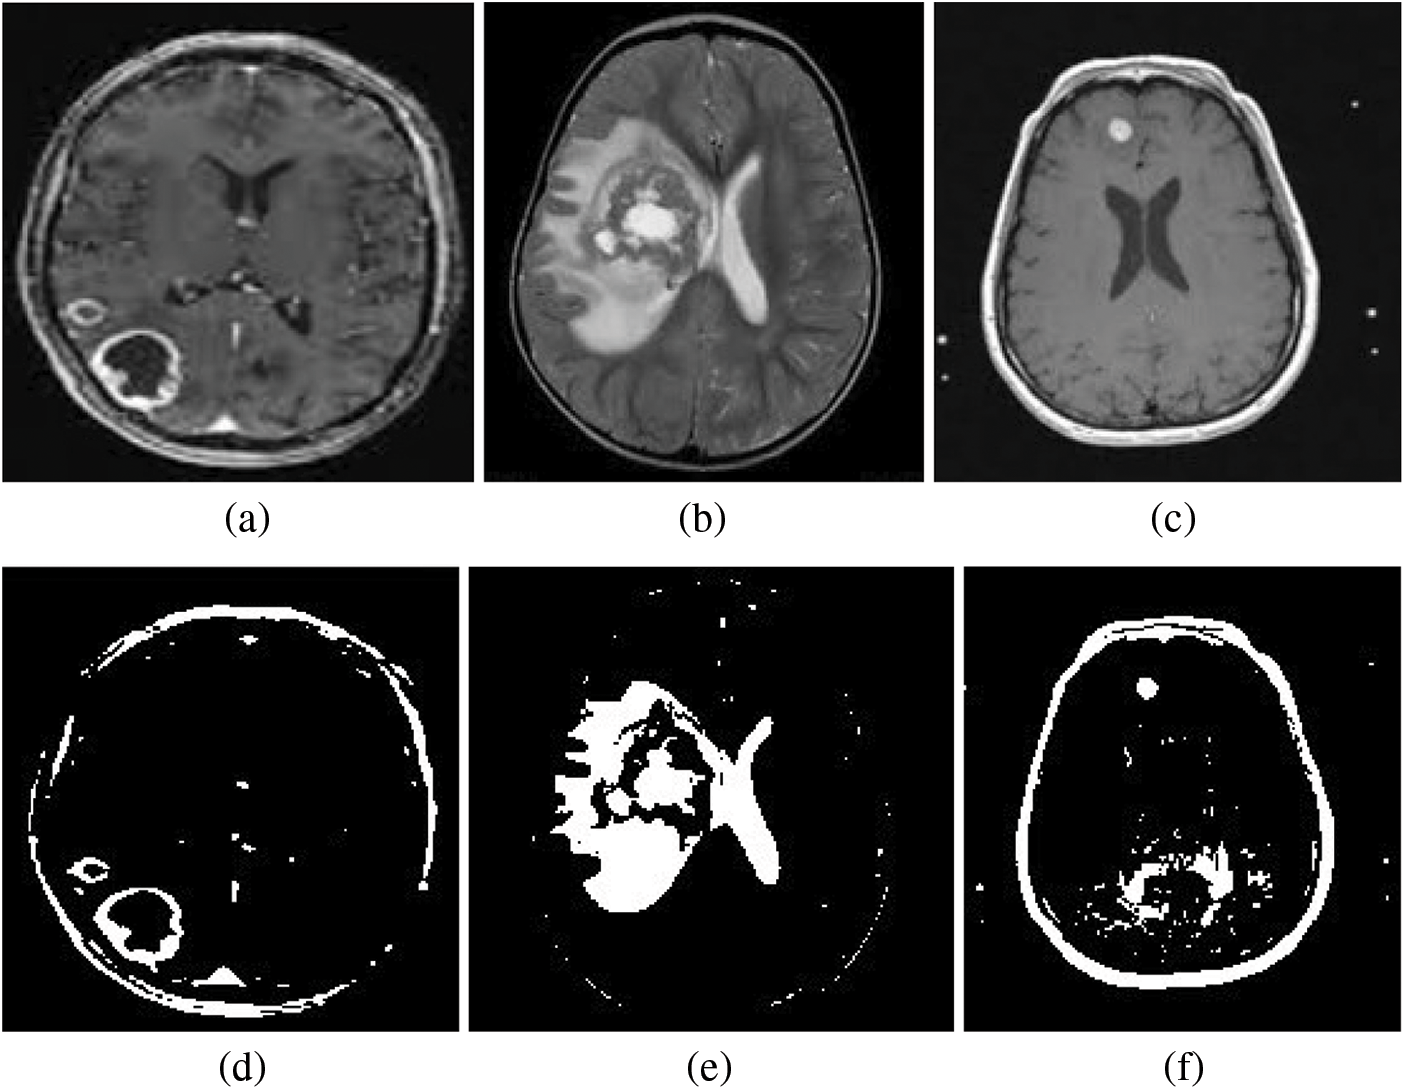

In the context of brain MRI images, FCM is employed to identify the actual pixels belonging to the tumor region. This pre-processing step is pivotal in improving the accuracy of subsequent classification methods, such as Support Vector Machine (SVM). By accurately delineating the tumor region through FCM, SVM can then effectively classify it. The FCM model essentially seeks to find the best cluster centers that represent the pixel distribution within the brain MRI images, with the goal of accurately segmenting the tumor regions. Specifically, the SVM classifier operates on features extracted from the segmented regions (FCM Output), particularly from the cluster 2 output image. Both the FCM cluster 1 output and cluster 2 output are depicted in the Fig. 5 as segmented images. The segmented images serve as the SVM classifier’s input, contributing to the accurate detection of the brain tumor region.

Figure 5: Segmentation results from the Fuzzy C-Means (FCM) algorithm are depicted, with Row 01 contains (a–c) illustrating the cluster 1 output and Row 02 contains (d–f) representing the cluster 2 output. The segmented 2 image, serving as the input to the Support Vector Machine (SVM) classifier, plays a pivotal role in achieving the accurate detection of the brain tumor region